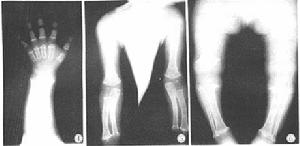

X線表現①顱蓋大,前額突出,頂骨及枕骨亦較隆突,但顱底短小,枕大孔變小而呈漏斗型,其直徑可能只有正常人的1/2。如伴發腦積水側腦室擴張。②長骨變短,骨幹厚,髓腔變小,骨骺可呈碎裂或不齊整。在膝關節部位,常見骨端呈“V”形分開,而骨骺的骨化中心正好嵌入這V形切跡之中。由於骨化中心靠近骨幹,使關節間隙有增寬的感覺。下肢弓形,腓骨長於脛骨,上肢尺骨長於橈骨。③椎體厚度減少,但脊柱全長的減少要比四肢長度的減少相對少很多。自第一腰椎至第五腰椎,椎弓間距離逐漸變小。脊髓造影可見椎管狹小,有多處椎間盤後突。④骨盆狹窄,骼骨扁而圓,各個徑均小,髖臼向後移,接近坐骨切跡,有髖內翻,髖臼與股骨頭大小不對稱。肋骨短,胸骨寬而厚。肩胛角不銳利,肩胛盂淺而小。

②長骨變短,骨幹厚,髓腔變小,骨骺可呈碎裂或不齊整。在膝關節部位,常見骨端呈“V”形分開,而骨骺的骨化中心正好嵌入這V形切跡之中。由於骨化中心靠近骨幹,使關節間隙有增寬的感覺。下肢弓形,腓骨長於脛骨,上肢尺骨長於橈骨。